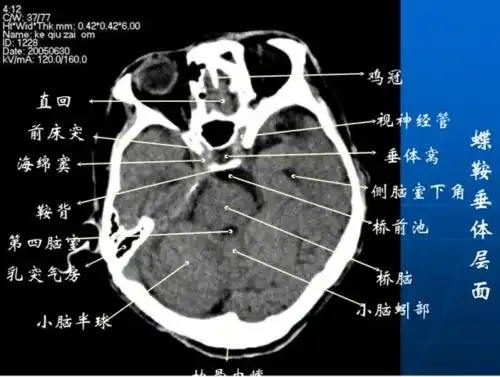

影像医生必须掌握的头颅ct解剖与常见出血梗死判读